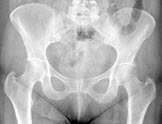

105、单项选择题

女,根据其正常骨盆影像图像,判断其最可能的年龄()

A.28岁左右

B.18岁左右

C.38岁左右

D.78岁左右

E.58岁左右

119、单项选择题

A.54岁左右

B.14岁左右

C.74岁左右

D.34岁左右

E.64岁左右